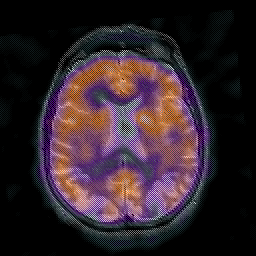

Alzheimer's disease: overlay -- Slice #32

[Home][Help][Clinical] Slice 32